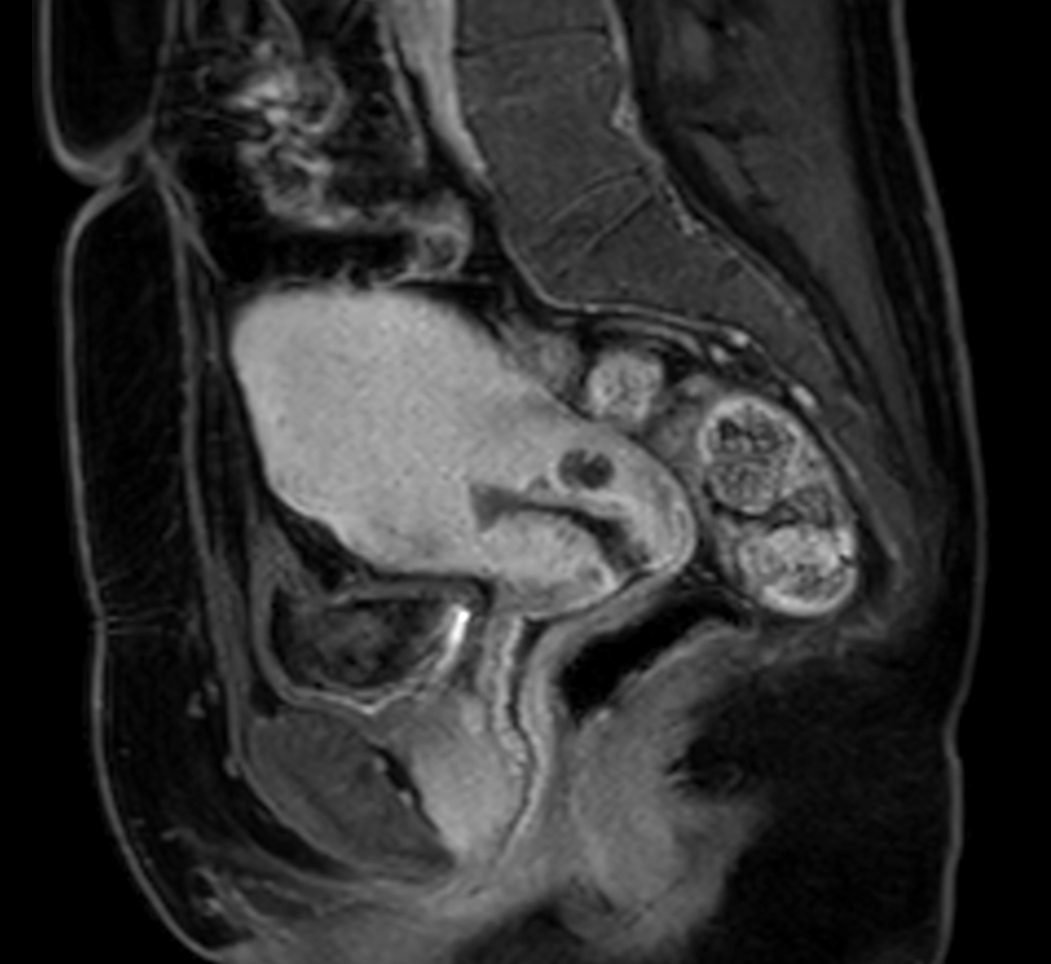

Sagittal MultiVane XD - T2w TSE

Sagittal mDIXON XD - T1w FFE plus gado (Water only)